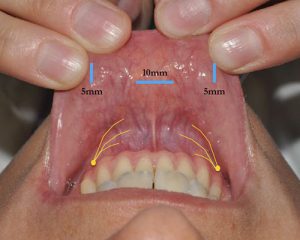

Endoskopowe operacje tarczycy metodą TOETVA

Technika endoskopowego wycięcia tarczycy TOETVA jest procedurą małoinwazyjną w której dostęp operacyjny do tarczycy następuje przez przedsionek jamy ustnej, a nie jak w klasycznej chirurgii tarczycy poprzez wykonanie cięcia w dolnej części szyi. Zabieg rozpoczyna założenie trzech trokarów: jednego o średnicy 10mm oraz dwóch o średnicy 5mm przez które następnie wprowadzane są narzędzia chirurgiczne. Wykonanie procedury metodą endoskopową z zastosowaniem neuromonitoringu śródoperacyjnego sprawia, że zabieg jest optymalnie bezpieczny dla pacjenta, pozwala mu na uniknięcie cięcia na skórze szyi i uzyskanie dobrego efektu kosmetycznego jak również pozwala na skuteczne skrócenie czasu rekonwalescencji. W ramach przygotowania do zabiegu metodą TOETVA rekomendowana jest wcześniejsza konsultacja stomatologiczna, która ma na celu wykluczenie ewentualnych ognisk zakażenia w jamie ustnej. Zabiegi metodą TOETVA w Szpitalu na Klinach realizuje prof. Marcin Barczyński wraz z zespołem.